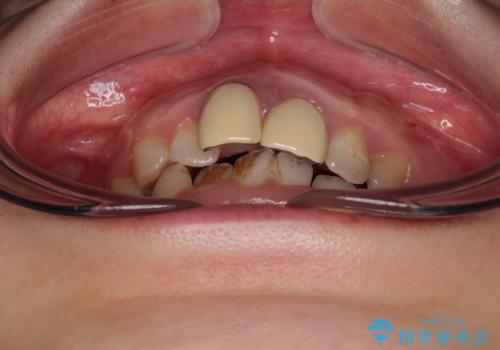

- 前歯のデコボコと、着色が著しい保険診療の前歯クラウンを気にして来院された患者様です。

左上の犬歯が埋伏しており、CT画像より萌出は困難と判断されたため、残存している歯にて歯列と咬合を整えることとしました。

マウスピース装着は煩わしいとのことで、表側のワイヤー装置にて矯正治療を行うこととしました。

前歯のクラウンは変色が顕著なため、矯正治療後にオールセラミッククラウンによる補綴治療を行うこととしました。

前歯のクラウンは、歯肉内深くに削り込まれており、歯肉の炎症が継続していたため、矯正治療後に歯周外科処置を行い、歯肉の腫れを改善させました。